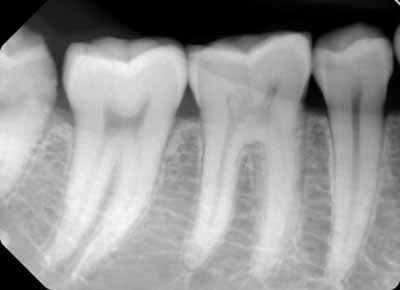

等角投影および平行投影から撮影された適切に配置された口腔内画像では、歯のさまざまな組織とその支持組織を区別できるはずです。歯の周囲では、歯槽突起内の海綿骨と緻密骨の両方を区別できるはずです(画像2を参照)。

X線画像では、被写体コントラスト(X線コントラスト)の違いによって、歯を構成する3つの異なる組織を区別できます。歯冠の外側を覆うエナメル質はミネラル含有量が最も高く、そのためX線写真では最もエックス線不透過性が高いように見えます。象牙質はエナメル質よりもミネラル含有量が少ないため、エックス線不透過性が低くなります。軟組織からなる歯髄は、エックス線透過性の外観を呈します (画像3を参照)。

歯の根の周囲には、繊維性結合組織からなる歯周靭帯があります。これは、根の表面に最も近い薄いエックス線透過性の隙間として描画されます。歯周靭帯に最も近い歯槽骨は、歯槽硬線と呼ばれる薄く緻密な骨組織で構成されています。この緻密骨は、歯の根面に沿って歯槽突起の緻密骨と融合する薄いエックス線不透過領域として描かれます (画像3を参照)。